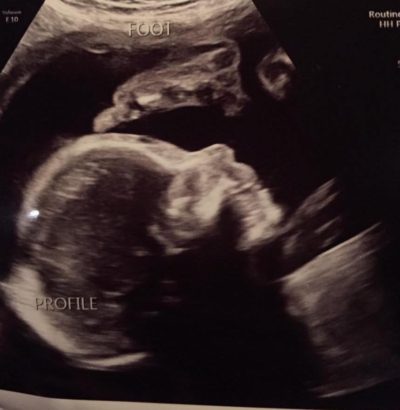

Nina’s pregnancy carried on as expected, with frequent ultrasounds and exams to ensure that she and the baby were healthy. She relished seeing little Owen on the monitor, watching him grow, and seeing his tiny heart beating. She received constant confirmation that he was growing excellently. Sometimes Nina would find herself back on Google, trying to mentally prepare for the eventuality that she would have a son with KS. Late into her pregnancy, she found an old blog from 2001 about a mom whose son had Klinefelter syndrome and whose family looked great. That blog linked her with XXY Facebook groups, and eventually Ryan and Living With XXY.